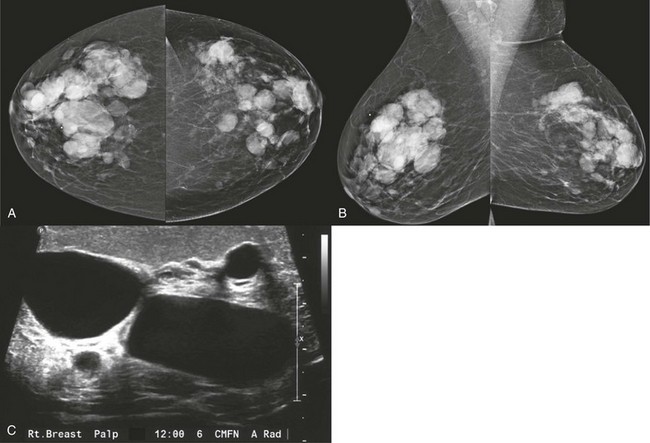

FIGURE 8-2 Multiple Cysts.

A 55-year-old woman with a newly palpable mass in her right breast (marker). A and B, There are multiple bilateral similar-appearing masses with circumscribed margins. When compared with previous mammograms, some masses had decreased in size while others showed enlargement. US targeted to the region of the newly palpable mass reveals multiple cysts (C). Sonographic evaluation of the remaining masses was considered unnecessary, and the patient was assigned BI-RADS 2.